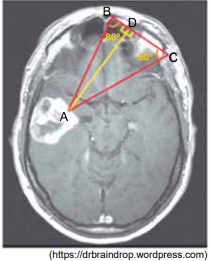

Questão 47 - Albert Einstein 2020 | Resolução Comentada | Akira Enem